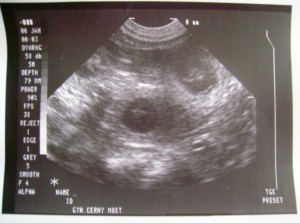

Jako nečekaný bonus jsme od pana doktora dostali vyfocená miminka (takovou fotku nemám ani já ze svých těhotenství (mám "pouze" video :o))

26.den